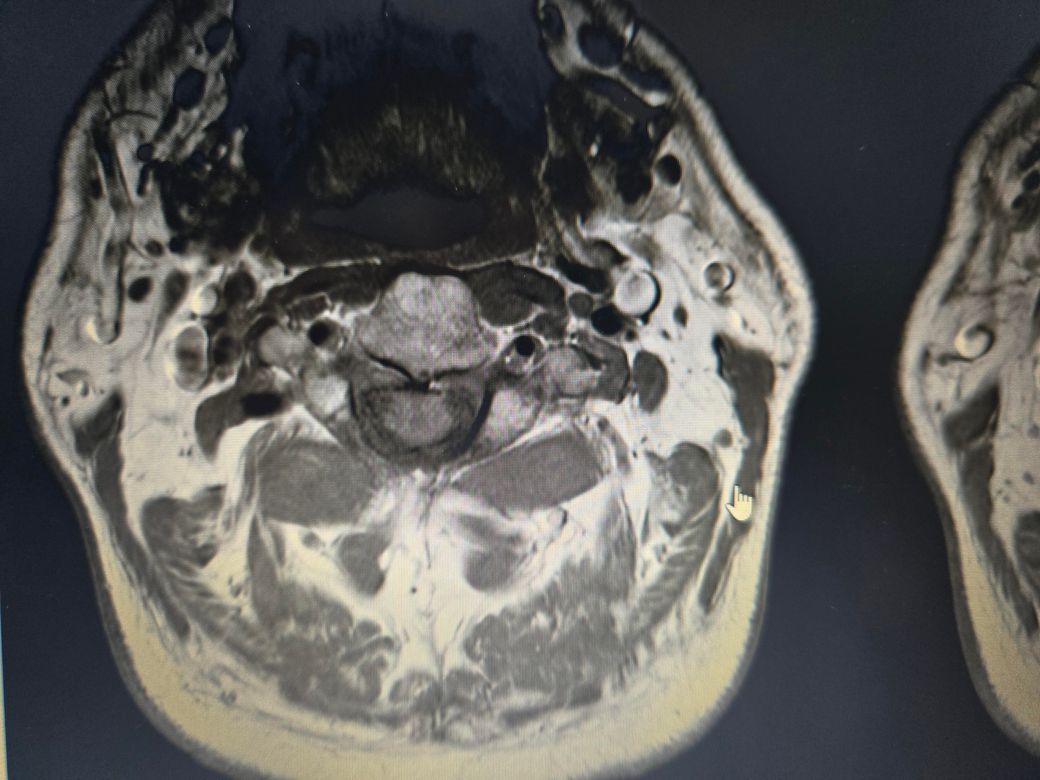

목디스크, 협착증 수술안해도되는건가요

목디스크 협착

정형외과에서는 디스크 협착증소견을 내고서는 마사지 잘하면된다는데, mri상으로도 심하지 않은건지궁금합니다

• 1번 째 사진